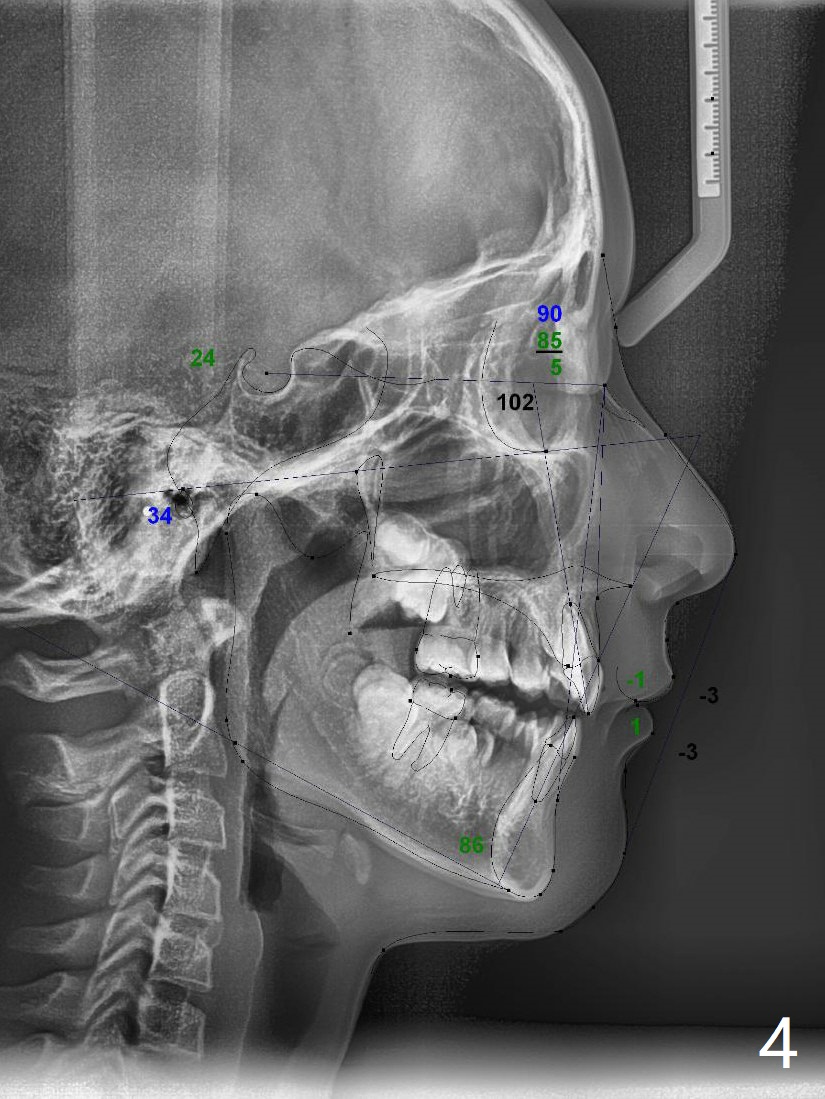

A 10-year-8-month-old woman presents to clinic with severe crowding (especially at the canines, Fig.1), but her facial profile is within normal limit (Fig.2,3) in spite of the fact that cephalometric tracing shows bimaxillary protrusion (Fig.4). Will 4 bicuspids' extraction affect her profile? Her mom requests immediate treatment, although the patient's oral hygiene is questionable.

Dear Dr. Shaughnessy: Can you review the following case? Is it too early to initiate the case as the mom wants? Should we extraction L Es first and 4 bi next? Or together now? After 1st bi ext, distalization of only 3s should not affect the facial profile? Thanks.

If the crowding is as severe as it appears, I would have no problem extracting the 1st premolars and Es prn. U will not change the profile much at all if any if severe crowding because you will have only small space to close. Do remember from the start that I will need Class I molars so do what it takes to end up there! If you fall short, you finish with xs overjet.Return to